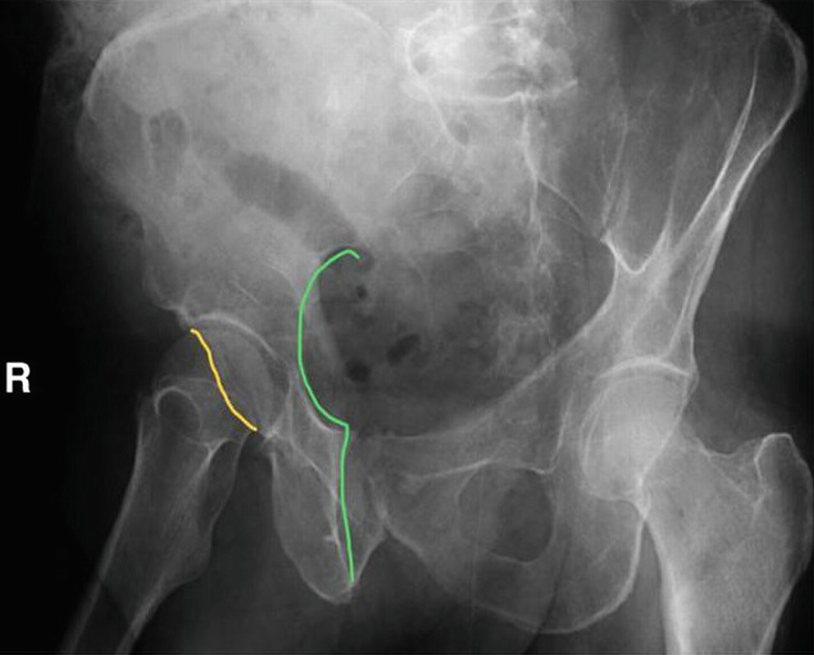

Thomas aquinas high school a roman catholic co educational college preparatory school has acquired national recognition for academic and athletic excellence. Posterior venous plexus injury in pelvic fractures can account for majority of blood loss. Corona mortis latin for crown of death is a common variant vascular anastomosis between the external iliac artery or deep inferior epigastric artery with the obturator arteryit is reported to be present in a third of patients on routine multi detector ct examination 14.

Laceration of corona mortis in 10 15. Knowledge of this variant vascular anastomosis is critical for surgical planning and in pelvic trauma as it is. 82 34954251 l 2 b select answer to see preferred response.

Connection between inferior epigastric branch of the external iliac vessls and the obturator vessels. Exposed and retracted early in the exposure. Lateral in comparision to tibial division most commonly injured neural structure during tha.